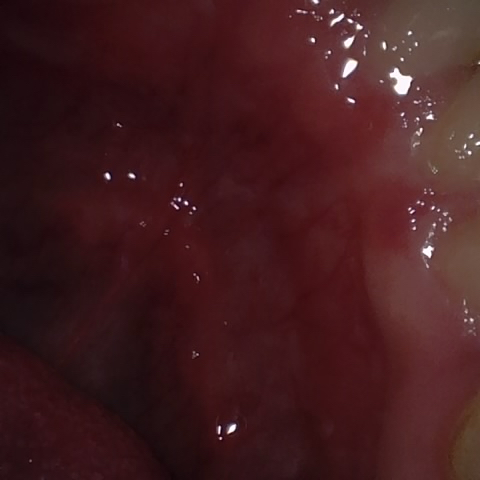

NHD20794

Annotated as "Bad"